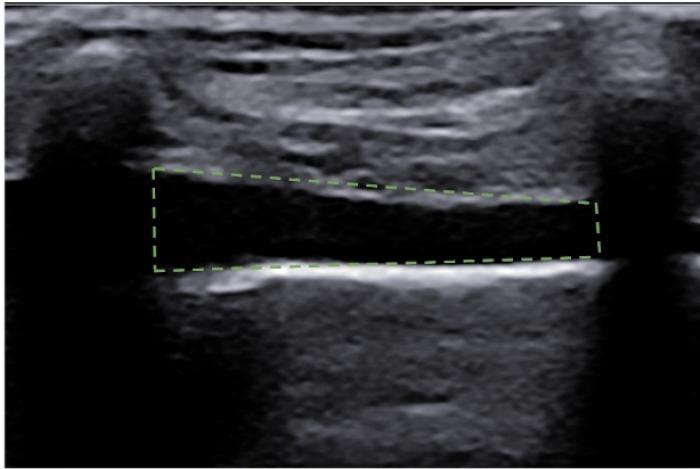

Signo del sinusoide y cuadrilátero

La presencia de pequeñas colecciones de fluido en el espacio pleural no siempre son del todo fáciles de evaluar, especialmente si el contenido en cuestión es lo suficientemente celular como para no visualizarse anecoico. El uso del modo M en estas circunstancias puede ser muy útil. Nos posicionamos con el transductor transversal en el espacio intercostal seleccionado (áreas más declives tienen mayor porcentaje de éxito puesto que el fluido desciende por gravedad), situamos el cursor y activamos el modo M, puesto que el pulmón no está en contacto en todo momento con la pared costal, la LP dibujará un movimiento sinusoidal en el registro en movimiento, muy diferente de la recta hiperecogénica que vemos en el tórax sano (Figura 9A-B).

Por contra, en modo B es posible visualizar lo que se llama signo del cuadrilátero, que es el área comprendida entre la pared costal (límite superior), costillas (laterales) y pleura visceral (límite inferior) dejando un aspecto poligonal en el foco con fluido (Figura 10A-B).